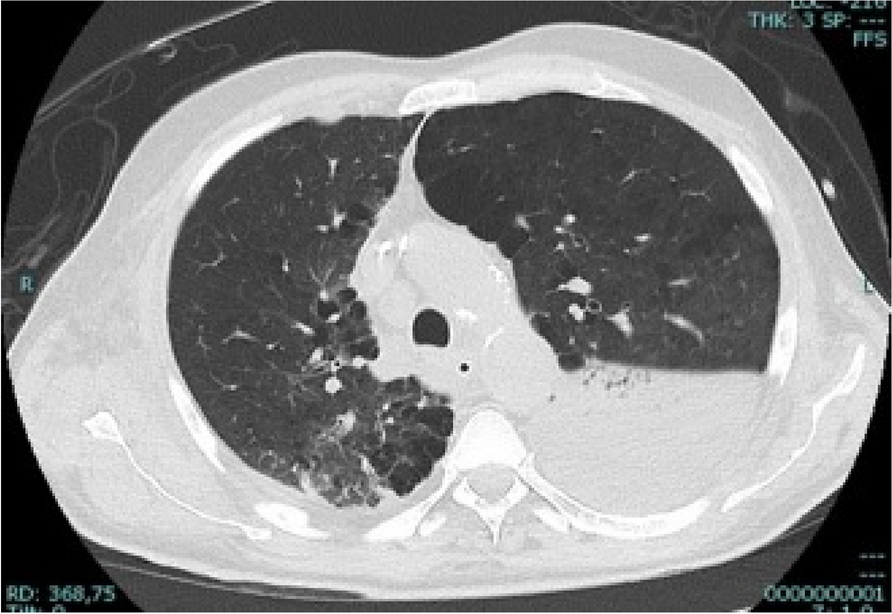

In this specific case, the patient, affected by L. Pneumophila, presented a PO2/FiO2 ratio between 100mmHg and 200mmHg, giving rise to a moderate ARDS panel according to Berlin Criteria (Image 1).

For this reason, we decided to use a non-invasive periprocedural ventilation mode, specifically the High Flow Nasal Cannula (HFNC), to reduce the risk of postoperative pulmonary complications due to invasive ventilation through endotracheal intubation (ETI).

Image 1 (abstract A9).

See text for description